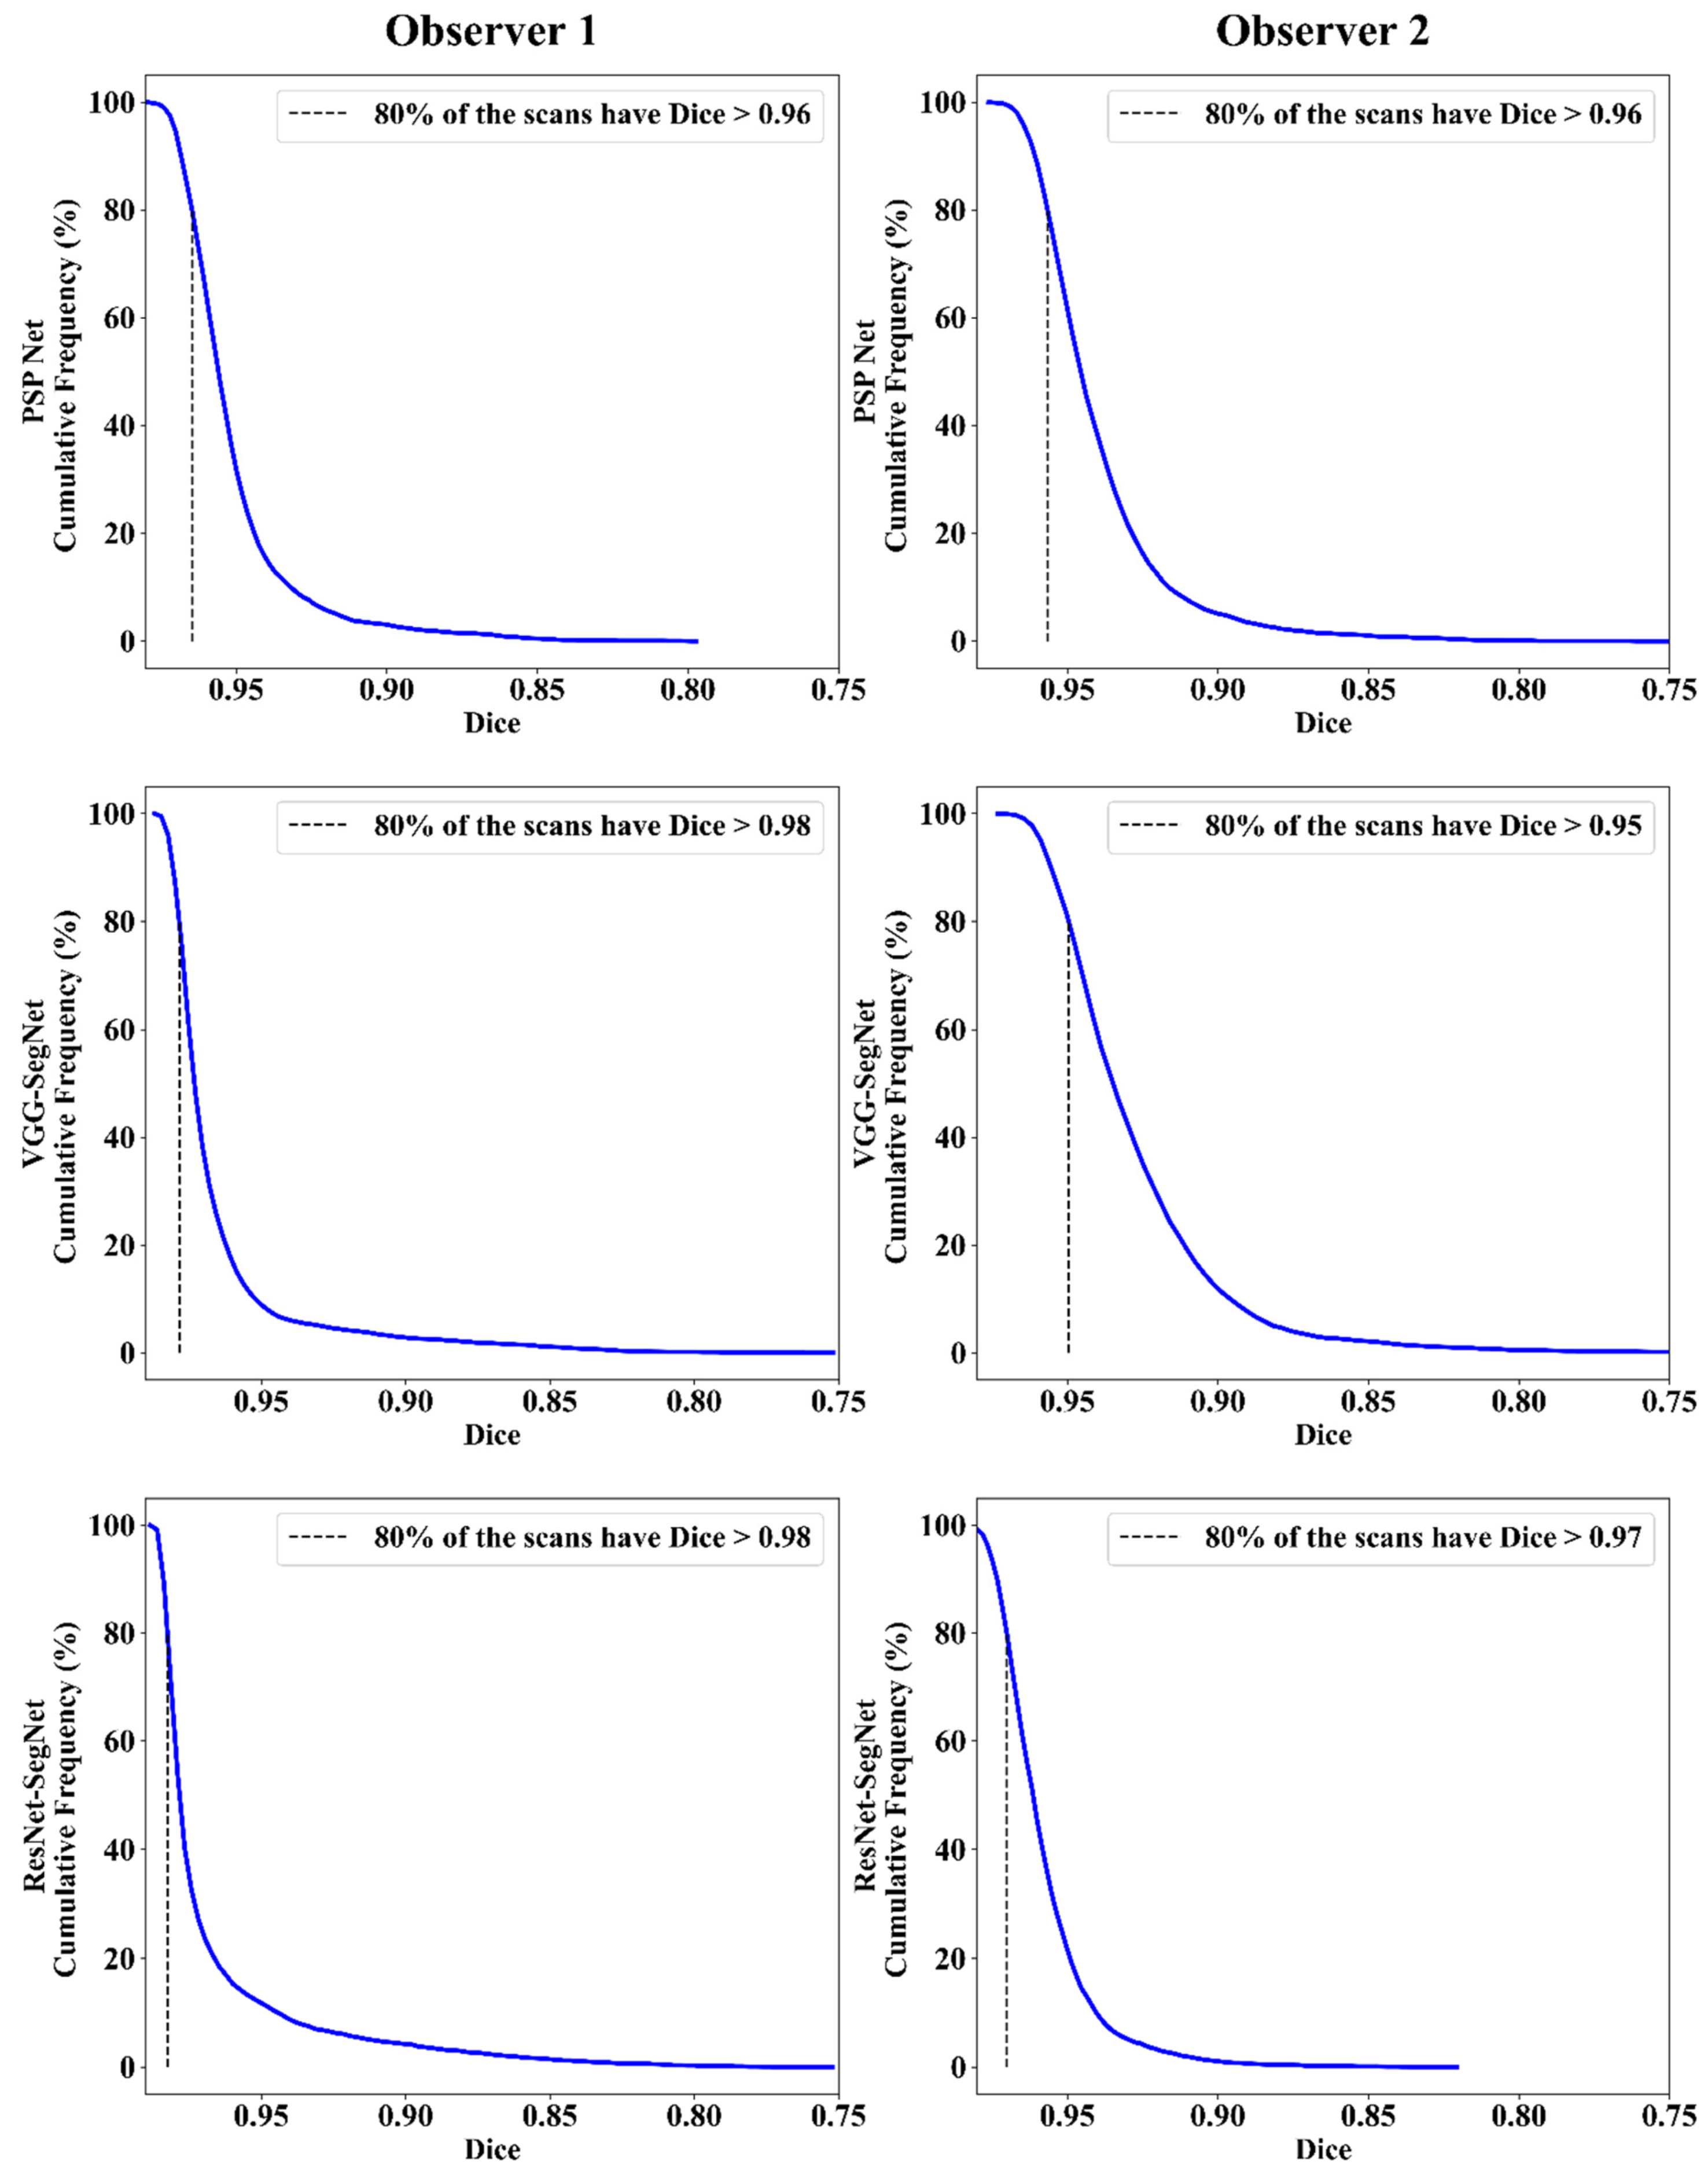

Cumulative Frequency Plot for Lung Area Error

Jaccard Index and Dice Similarity

| Observer 1 | Observer 2 | Mean Obs. 1 & Obs. 2 | |||||||

|---|---|---|---|---|---|---|---|---|---|

| Attributes | PSP Net | VGG-SegNet | ResNet-SegNet | PSP Net | VGG-SegNet | ResNet-SegNet | PSP Net | VGG-SegNet | ResNet-SegNet |

| DS | 0.96 | 0.98 | 0.98 | 0.96 | 0.95 | 0.97 | 0.96 | 0.97 | 0.98 |

| JI | 0.93 | 0.96 | 0.97 | 0.92 | 0.9 | 0.94 | 0.93 | 0.93 | 0.96 |